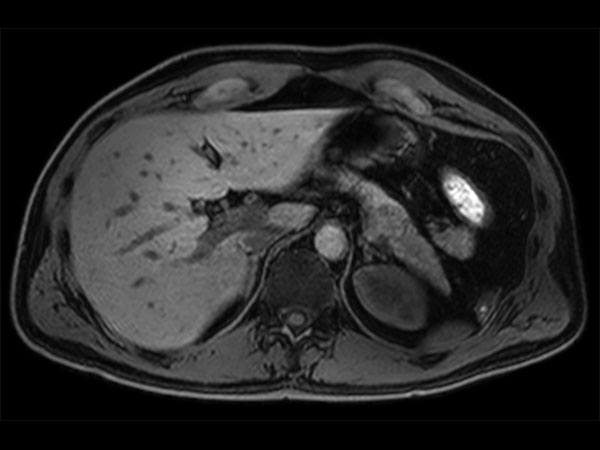

Advanced Liver MR - mDIXON Quant

University of Michigan Hospital, Ann Arbor, USA